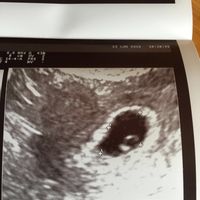

Ecco il mio pezzettino/a

Ecco a voi la prima ecografia speriamo bene via